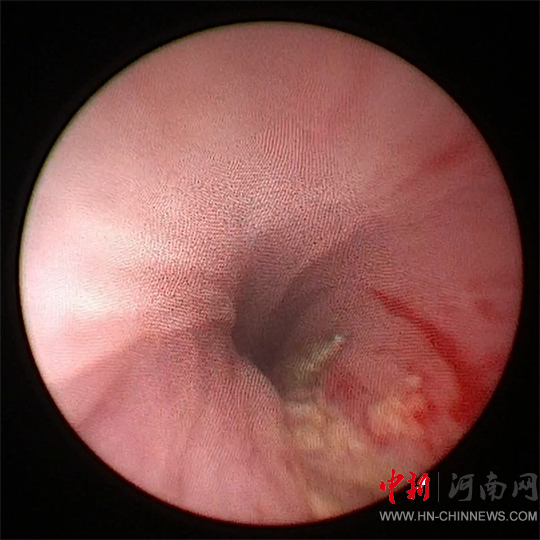

團隊決定嘗試

經(jīng)尿道應(yīng)用

小兒輸尿管鏡微創(chuàng)手術(shù)

將鋼針取出

然而,手術(shù)面臨

患兒尿道較細

鋼針堅硬且長

刺入尿道組織較深等問題